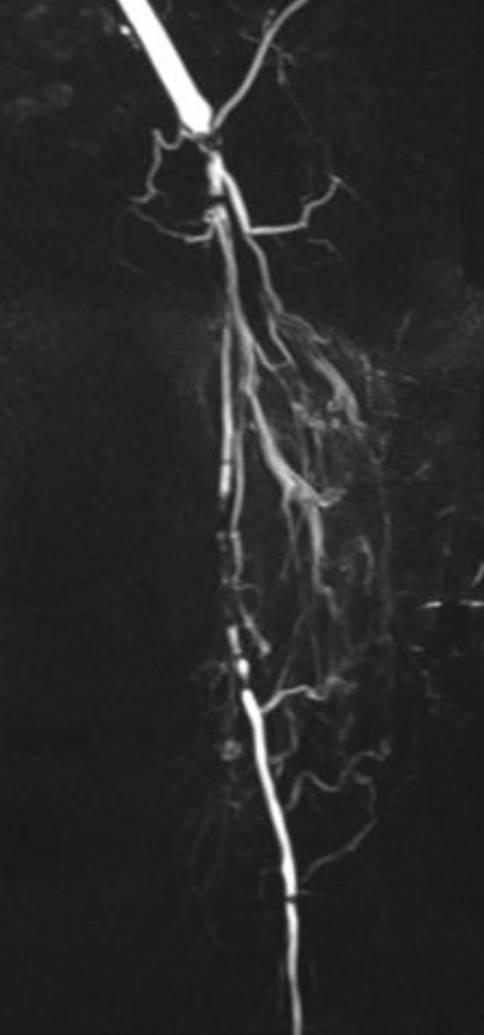

[糖尿病足综合征 - 第2部分:血运重建、治疗选择、护理结构、复发预防]

[Diabetic foot syndrome-Part 2 : Revascularization, treatment alternatives, care structures, recurrency prophylaxis].

Diabetic foot syndrome (DFS) is the most frequent reason for major amputations in Germany. The majority of foot lesions are triggered by repetitive pressure in diabetic polyneuropathy. Peripheral arterial occlusive disease (PAOD) impairs wound healing and is the main risk factor for amputations. The treatment of wounds and infections as well as timely revascularization are decisive. The use of endovascular and vascular surgical methods depends on the distribution pattern and length of the occlusion processes. Both procedures are complementary. Bypass surgery is of great importance for neuroischemic DFS. Multidisciplinary centers that provide revascularization in DFS can achieve an improvement of arterial blood flow in 90% of the cases and reduce the amputation rate by up to 80%. Due to the high recurrence rate of diabetic foot lesions, measures for secondary prophylaxis are of exceptional importance (podological and orthopedic technical care, foot surgery).

糖尿病足综合征(DFS)是德国进行大截肢手术最常见的原因。大多数足部病变是由糖尿病多发性神经病变中的反复压力引发的。外周动脉闭塞性疾病(PAOD)会损害伤口愈合,是截肢的主要危险因素。伤口和感染的治疗以及及时的血运重建是决定性的。血管内和血管外科方法的使用取决于闭塞过程的分布模式和长度。这两种手术方法相辅相成。旁路手术对神经缺血性DFS非常重要。在DFS中提供血运重建的多学科中心在90%的病例中可实现动脉血流改善,并将截肢率降低多达80%。由于糖尿病足病变的复发率很高,二级预防措施尤为重要(足部护理和矫形技术护理、足部手术)。